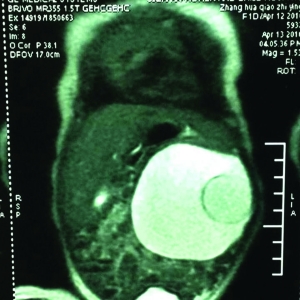

王壽青說,臨床調(diào)查顯示,寄生胎的發(fā)病幾率約為百萬分之一。從苗苗入院時(shí)的B超,可以清楚地看到她腹中10厘米左右的囊性包塊,可以看到胚胎的頭、腿、脊柱。“因?yàn)榕咛ヒ呀?jīng)部分壞死,留在肚子里可能會(huì)讓主體感染。同時(shí),由于胚胎與主體血管相通,會(huì)分散主體吸收的營養(yǎng),隨著主體長大,形成惡性腫瘤。”王壽青說,基于此,4月19日,他們給苗苗做了手術(shù)。手術(shù)時(shí),醫(yī)生們先將囊性包塊中近200ml的水取出,之后又將胚胎順利取出。